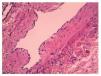

En su estancia se ordenaron nuevos estudios de laboratorio con los siguientes resultados: hemoglobina 12.3 g/ dl, hematocrito 37.6%, hemoglobina corpuscular media 24.6 pg, volumen corpuscular medio 75.5 fl, leucocitos 123,000/mm3, plaquetas 503,000/mm3. Glucosa 103 mg/dl, aspartato aminotransferasa (AST) 36.7 UI/l, alanina amino-transferasa (ALT) 20.8 UI/l, fosfatasa alcalina 218 UI/l, DHL 573 UI/l, antígeno carcinoembrionario 1.8 μg/l, gonadotrofina coriónica 0.100 mlU/ml, alfa fetoproteína 5.0 UI/ml, CA 125 31.6 UI. La tomografía axial computarizada (TAC) abdominal reportó masa quística con lóbulos que desplaza de manera anterior y hacia la izquierda las asas intestinales (fig. 2).

Figura 2 Tomografía axial computarizada de abdomen. Se observó una masa quística con lóbulos que desplaza de manera anterior y hacia la izquierda las asas intestinales.